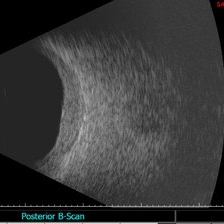

B scan ultrasound shows the thickened choroid

Condition/keywords: choroidal thickening, Sturge-Weber syndrome